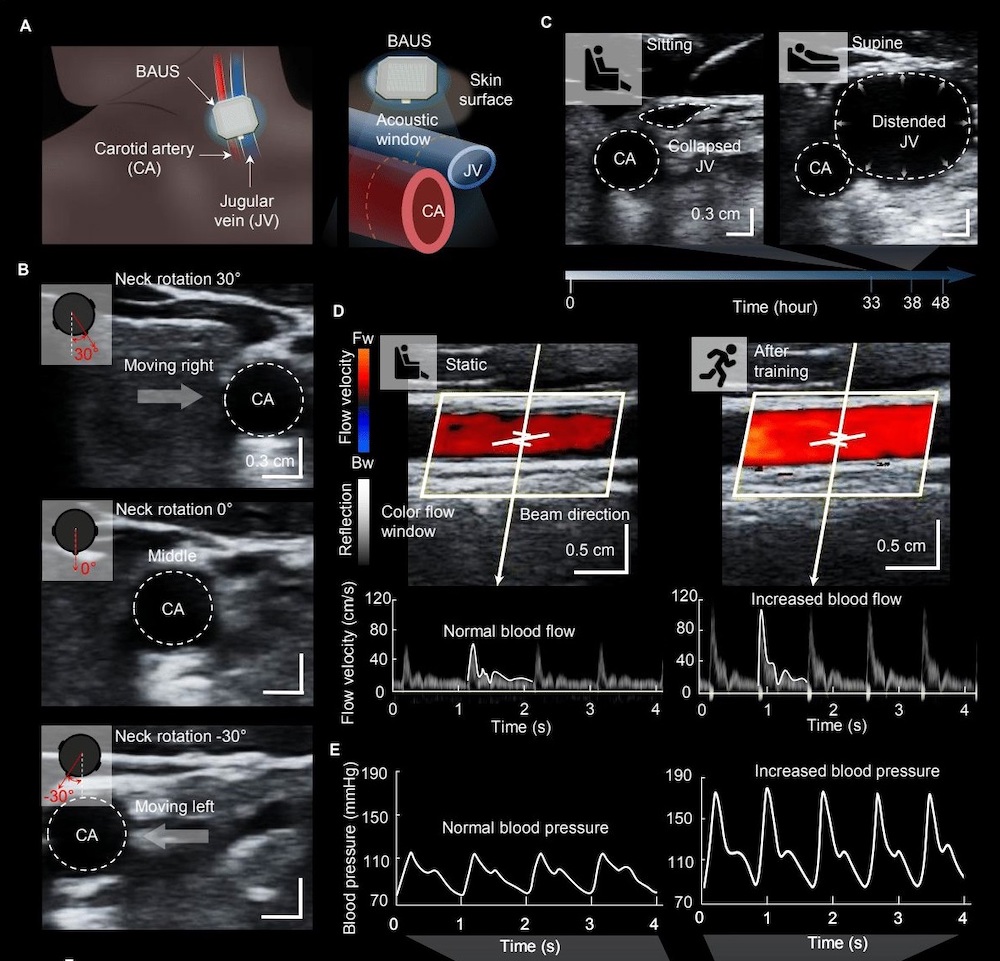

A and B The wireless Doppler ultrasound patch.... Download Scientific Diagram Ultrasound Patch Imaging in a paper published today in science, zhao and his team describe their development of a tiny ultrasound patch that, when stuck to the skin, can. this fully wireless ultrasound patch, which can capture detailed medical information and wirelessly transmit the data to a smart device, could. mit engineers designed an adhesive patch that produces ultrasound images. Ultrasound Patch Imaging.